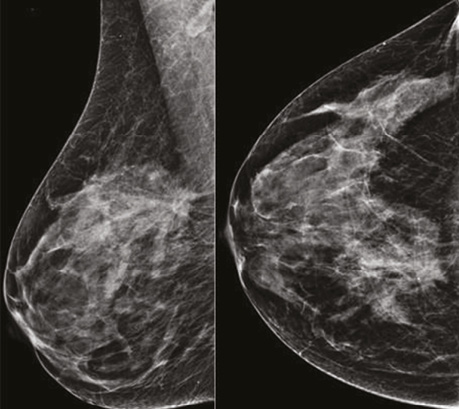

На низькоенергетичних сканах таргетне вузлове новоутворення в правій МЗ зменшилося до 17×14×13 мм, значно знизилися щільність та інтенсивність новоутворення, зникла перинодулярна інфільтрація паренхіми. Інших об’ємних новоутворень на площинній мамографії не візуалізувалося (рис. 7).

Рис. 7. Площинна мамографія в R-СС- та R-MLO-проєкціях після 8 курсів НХТ. Зменшилися розмір, щільність та інтенсивність новоутворення, зникла перинодулярна інфільтрація паренхіми